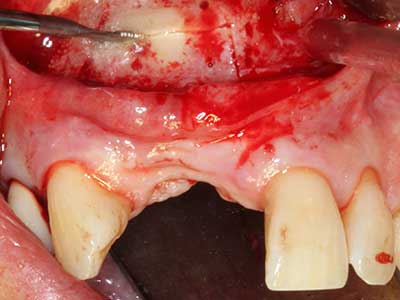

Bone tissue is not simply a mineral structure but also contains a substantial proportion of collagen fibres. This means it not only has good compressive strength but also a degree of flexibility, which can be taken advantage of when performing bone augmentations. In the classical expansion procedure using bone splitting, the atrophied alveolar ridge is split longitudinally and carefully expanded after reaching an adequate osteotomy depth (Fig. 13-16), ideally without substantial removal of the periosteum (Brugnami, Caiazzo et al. 2014, Stricker, Fleiner et al. 2014). Screw and plate systems with increasing expansion distance have proven effective in separating the two bone lamellae while remaining below the fracture threshold. In general, residual bone widths of at least 3–4 mm are required (Chiapasco, Zaniboni et al. 2006) to guarantee adequate flexibility and sufficient bone coverage of the future implants. If necessary, a vertical relief osteotomy on one or both sides can improve flexibility. A combination with additional augmentation techniques, particularly on the buccal side, has been described as an alternative to the classical technique.

Fig. 13: Adequate irrigation with the 4-mm residual bone width is essential for this 52-year-old patient during the bone splitting.

Fig. 14: Placement of four tapered RSX implants (Bego Implant Systems, Bremen).